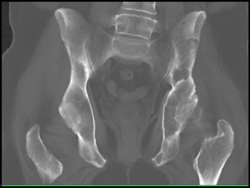

Myeloma